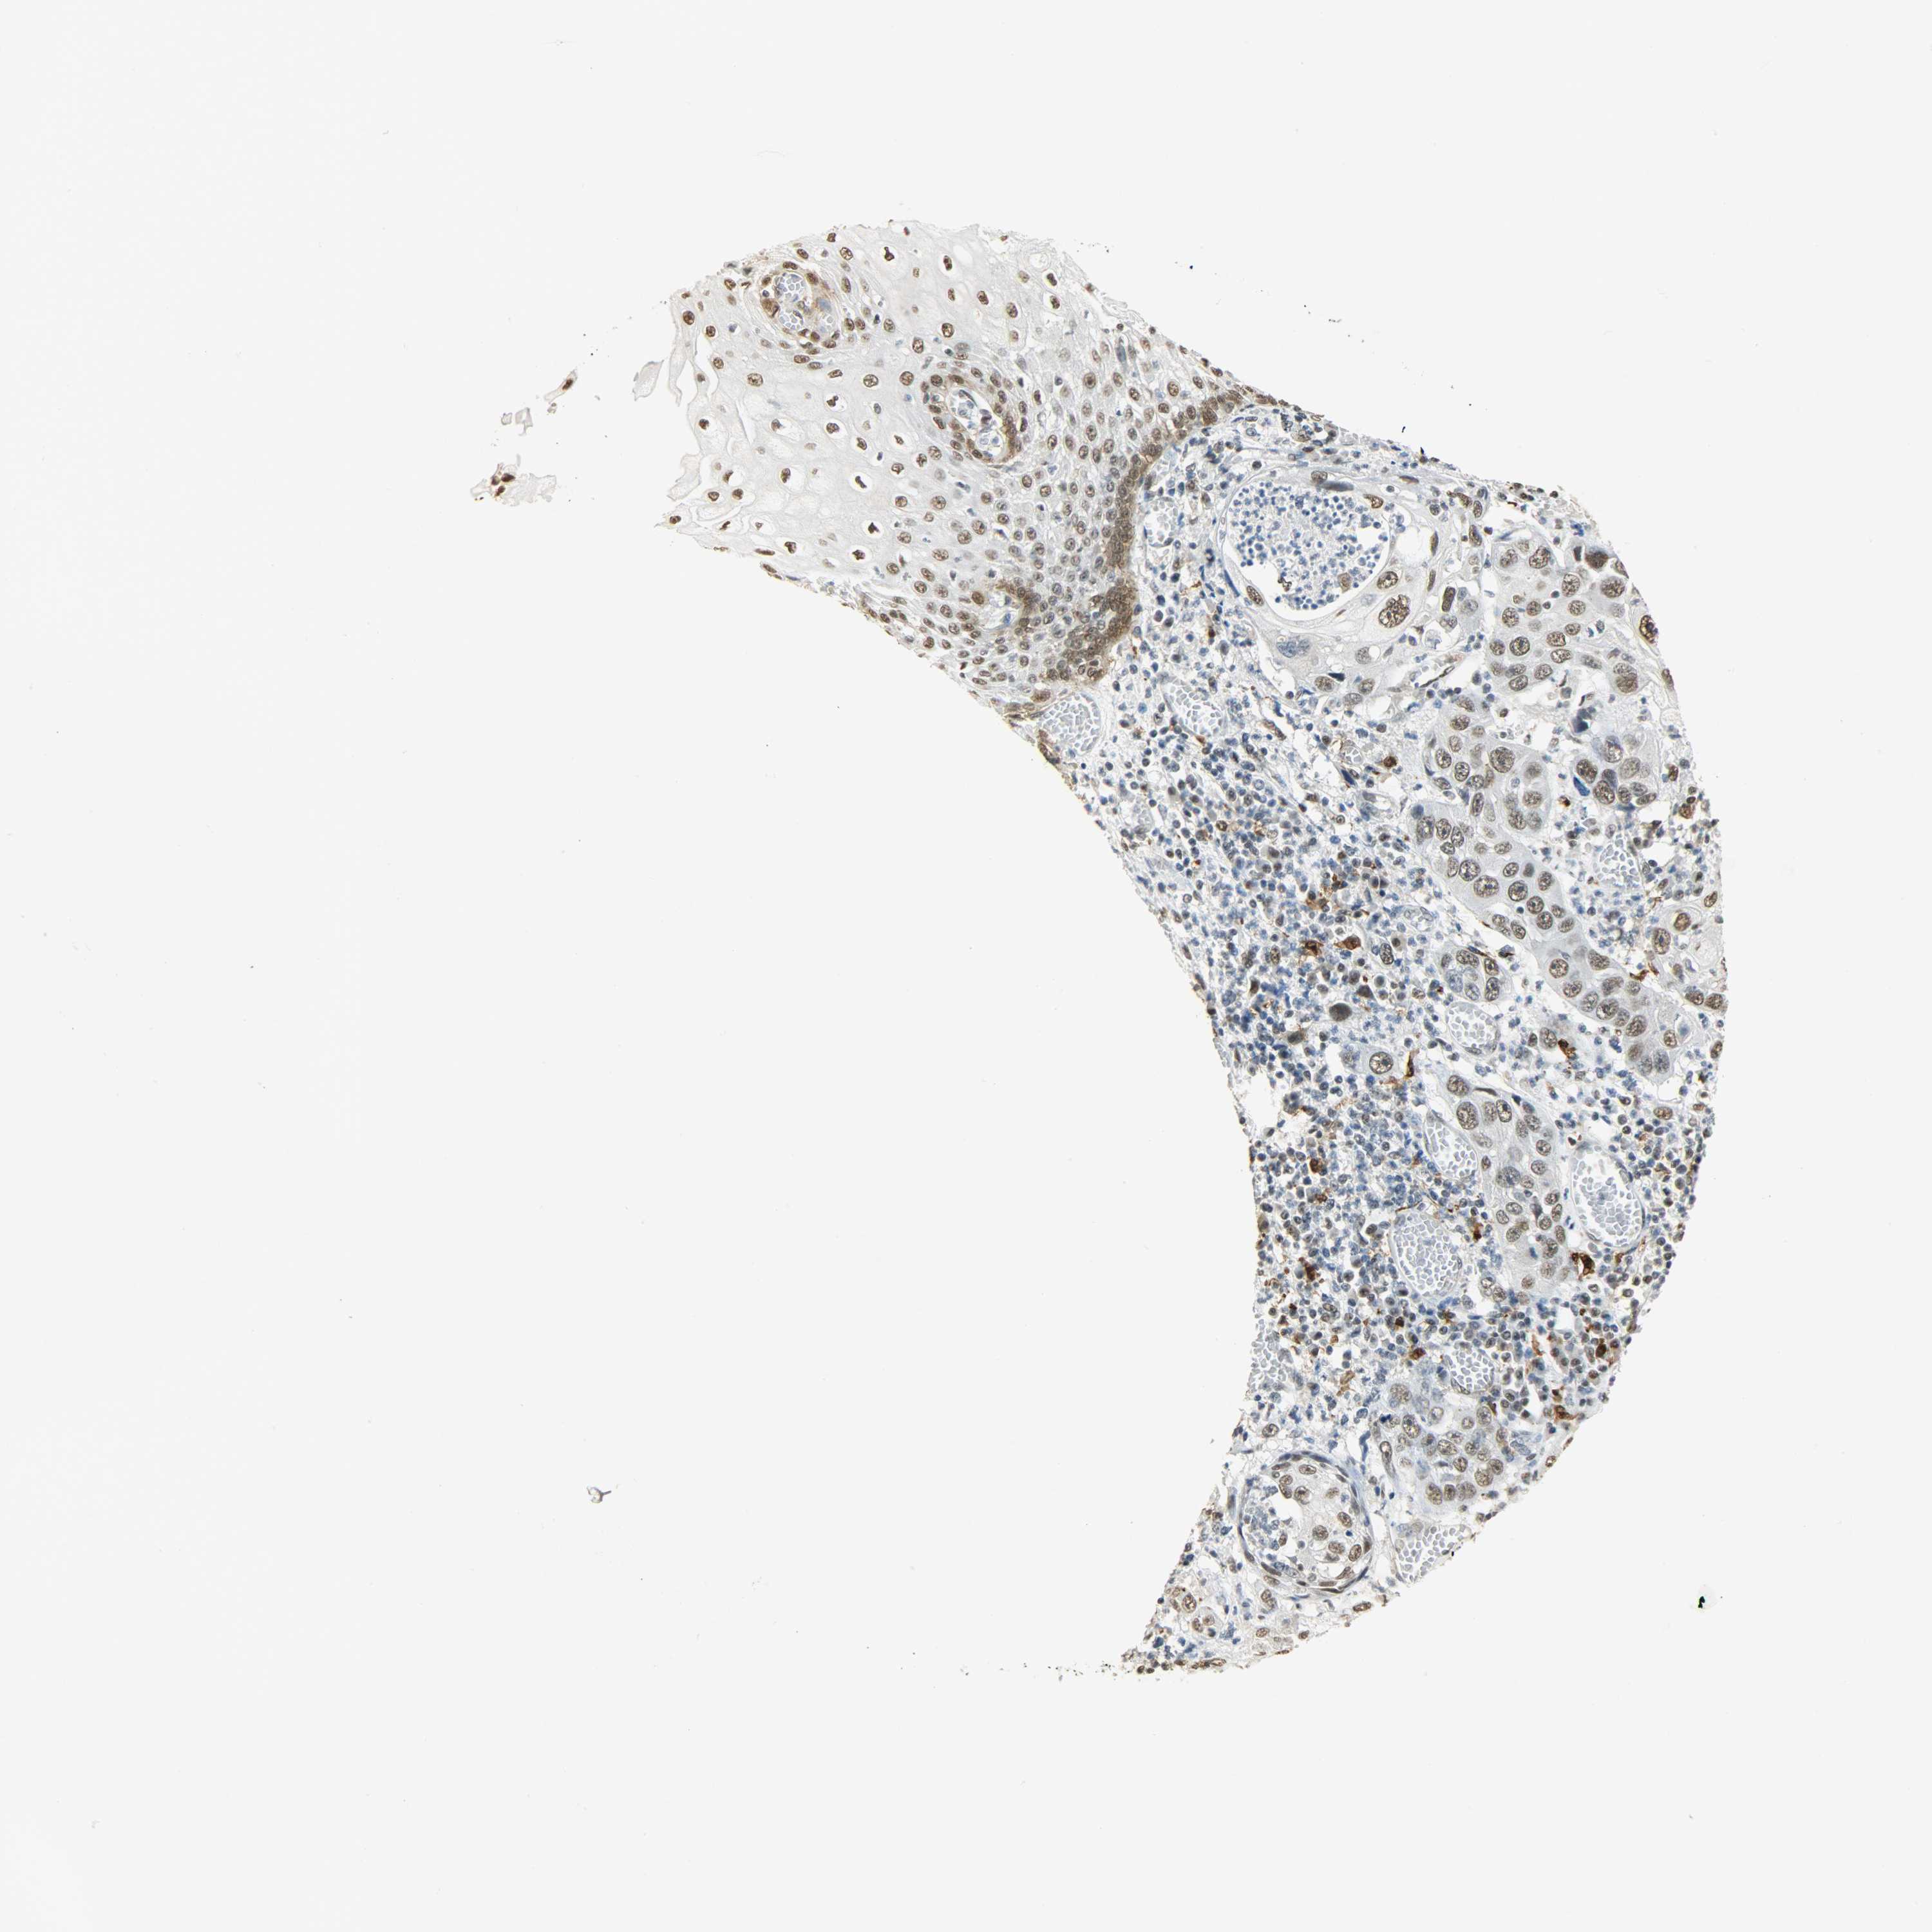

ESOPHAGUS - Antibody stainingi

Antibody staining in the annotated cell types in the current human tissue is reported as not detected, low, medium, or high, based on conventional immunohistochemistry profiling in selected tissues. This score is based on the combination of the staining intensity and fraction of stained cells.

Each image is clickable and will lead to virtual microscopy that enables deeper exploration of all samples and also displays staining intensity scores, fraction scores and subcellular localization as well as patient and tissue information for each sample.

Antibody HPA004765Antibody CAB000143Antibody CAB001995

Squamous epithelial cells MediumMediumLow